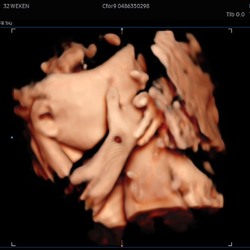

Hallo, ik heb Adenomyose. Dit zijn slijmen in de spieren van de baarmoeder waardoor het de innesteling enorm bemoeilijkt door de ontstoken slijmen. Heb hierdoor ook tal van miskramen gehad. Ik ben nu zwanger en neem Medrol 16mg, Progynova en asaflow. We wachten af 😇